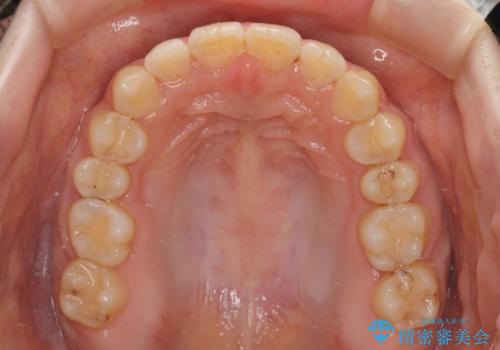

- 矯正装置

- 審美装置

- 大学病院にて装置を装着したものの、治療が十分に受けることができないとのことで転院をされた患者様です。

上顎歯列が前方にあり、口元が閉じにくくなっていたため、既に装着されている装置を使用して上顎歯列全体を後方に移動させていくこととしました。

舌の突出癖の影響か、なかなかスペースが閉じきらず、治療期間は予定よりも長期間となりました。